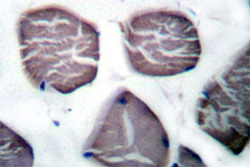

PAB27015 IHC

Method: